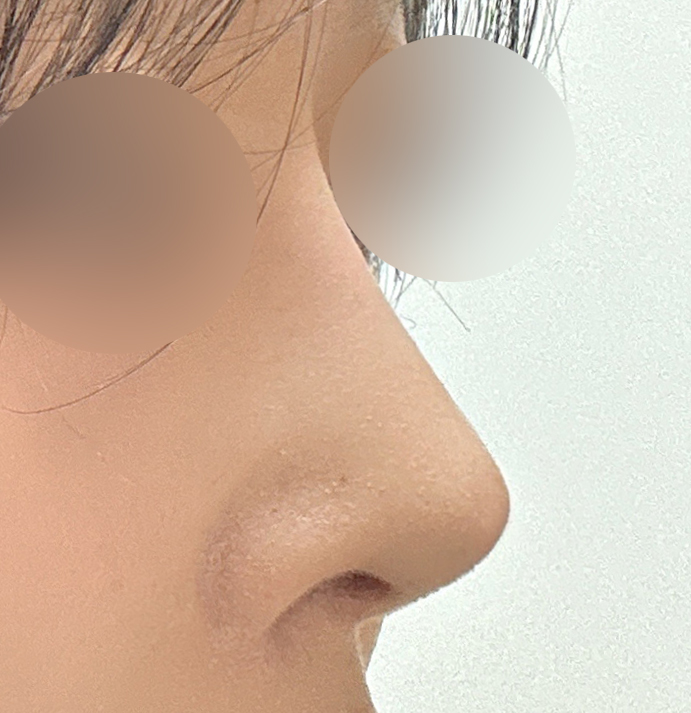

실리콘, 비중격, 귀연골, 기증늑연골사용해서

수술했고 이물질제거와 복코, 용코교정한지

3주차 됐는데요

벌써부터 너무 자연스럽고

평소 고민이었던 용코도 정말 많이 교정되고

자연스럽고 화려한 코라인이 나와서